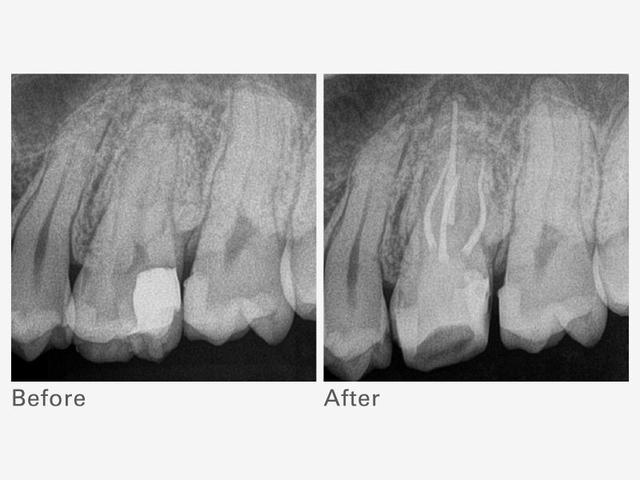

Технологія Root ZX. Вбудований апекслокатор, здатний проводити високоточне вимірювання незважаючи на те, сухий чи вологий канал, дозволяє виконувати лікування, постійно контролюючи положення файлу.

TriAuto ZX2+ також забезпечує численні функції безпеки, використовуючи перевірену точність Root ZX для зупинки обертання та запобігання надмірному використанню інструментів у кореневому каналі.